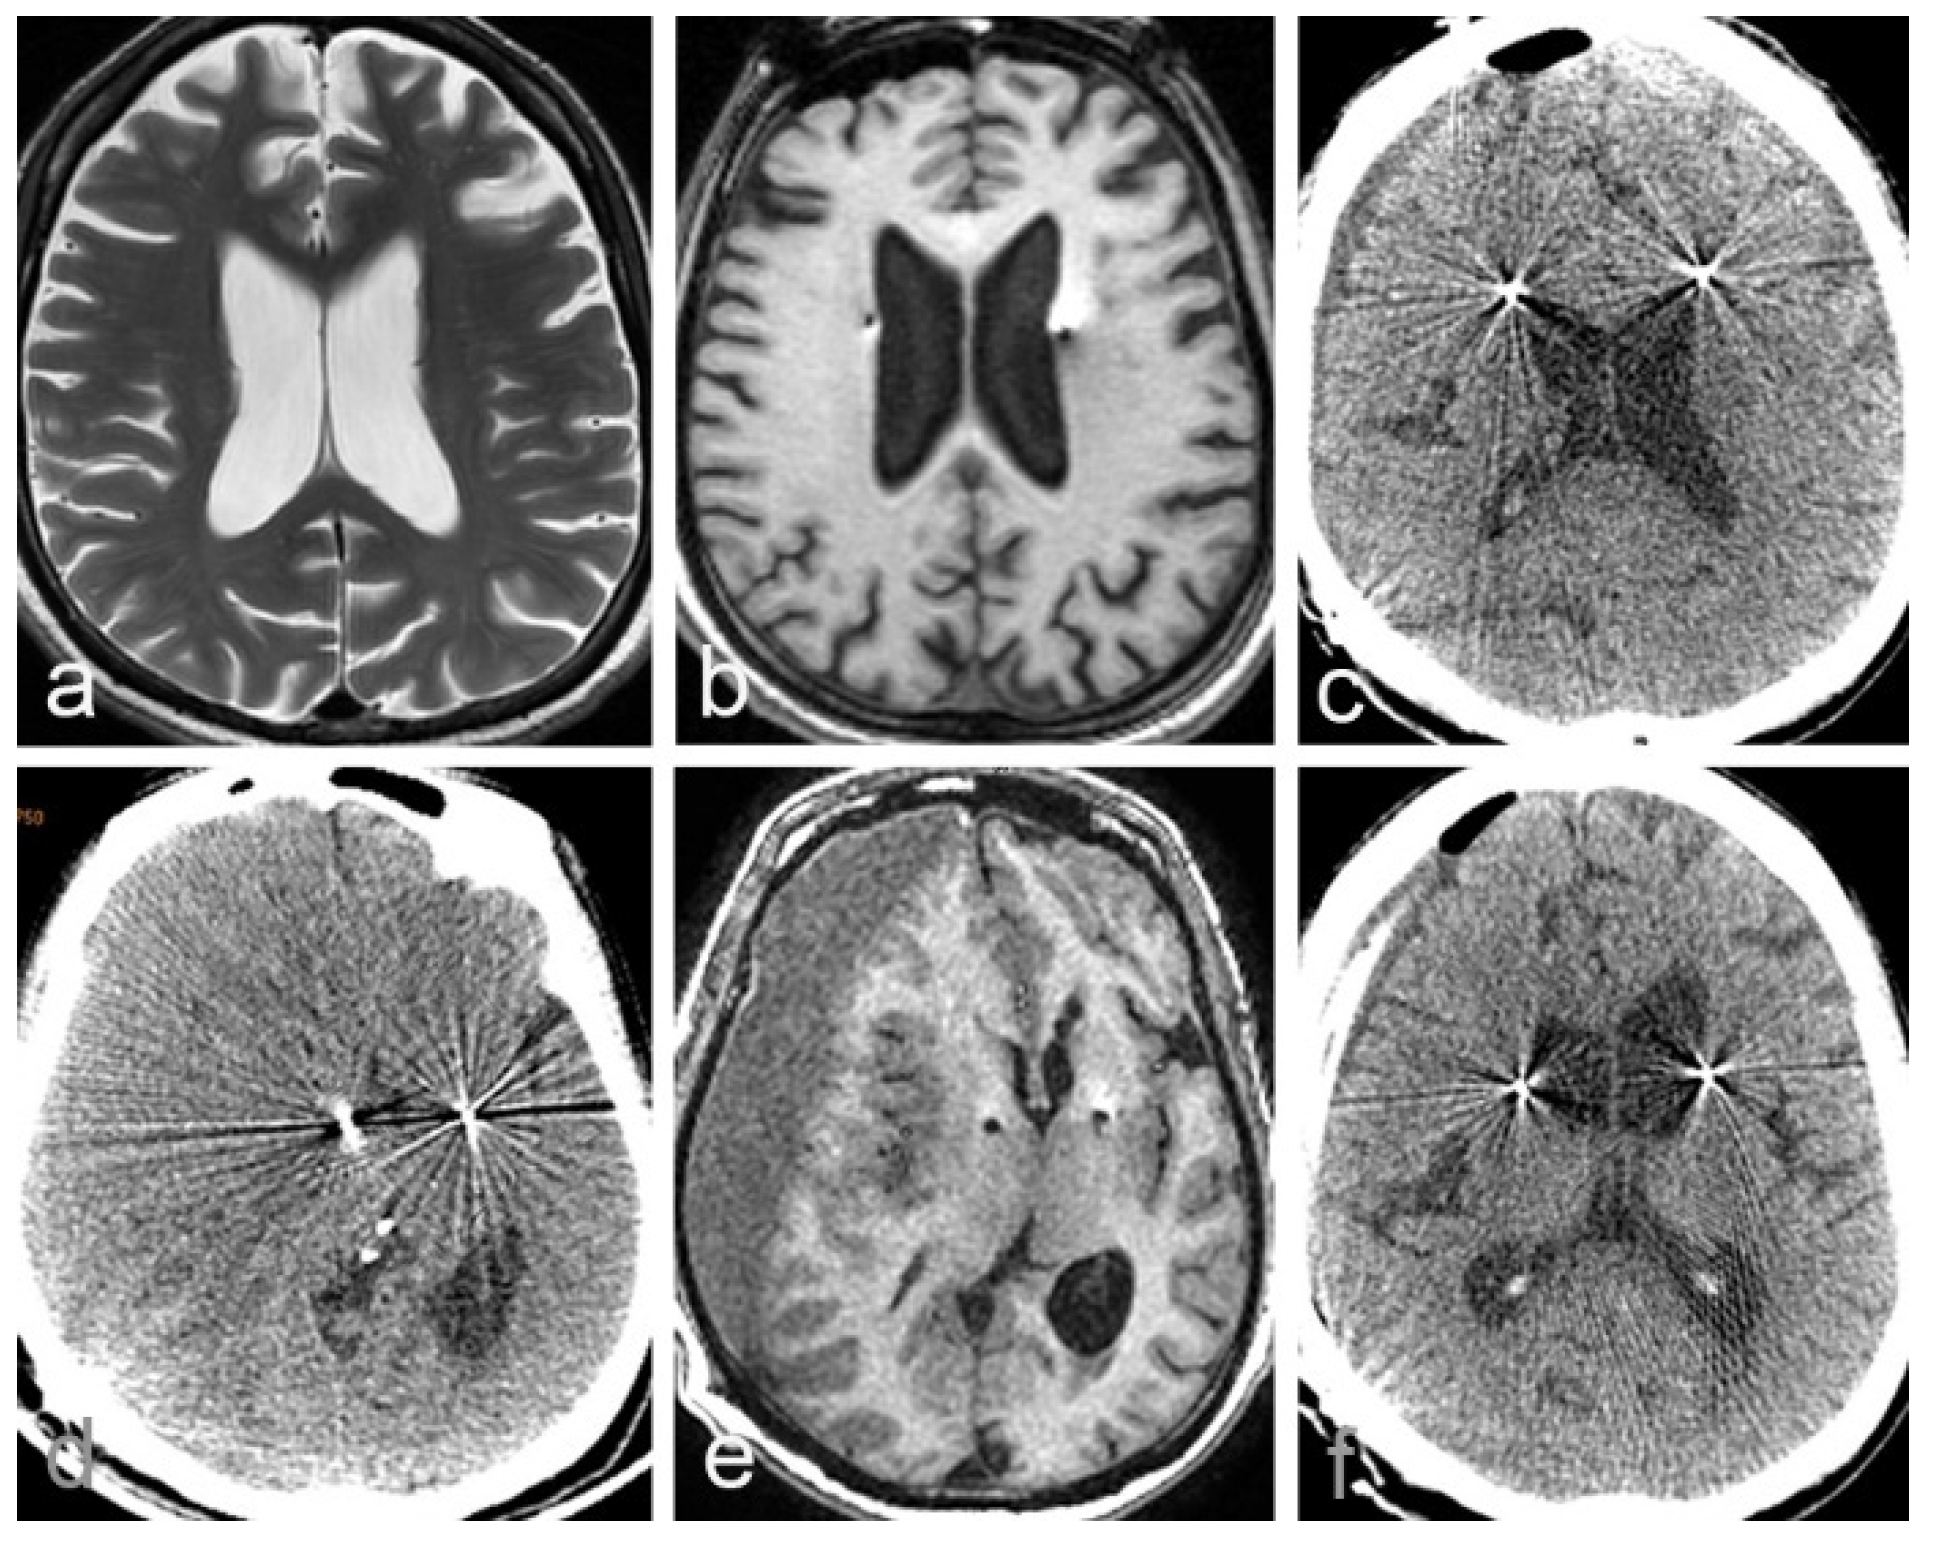

2.1. Case 1

2.2. Case 2

| Case 1 | 62 | F | Parkison’s disease | GPI | Yes | Yes | 36 days | description | poor |

| Case 2 | 56 | M | Alzheimer’s disease | fornix | Yes | Yes | 49 days | description | poor |